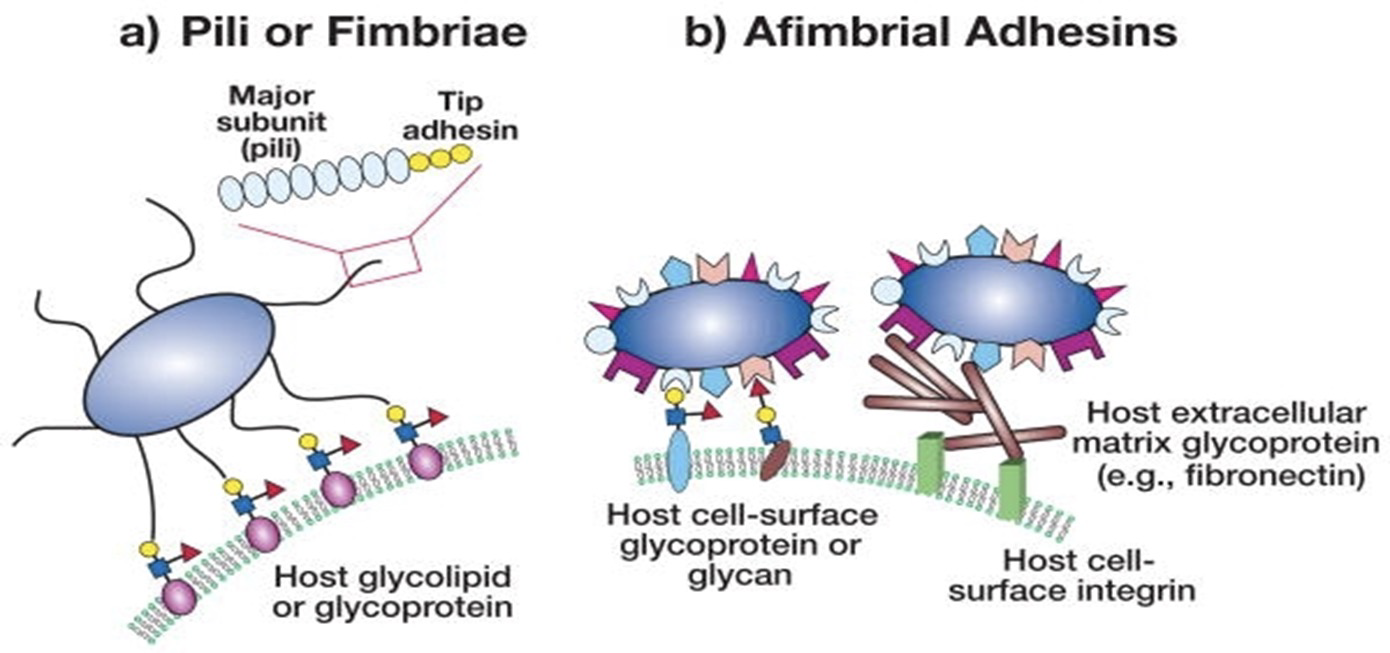

致病

黏細胞

gram’s negative: Pili, Fimbriae